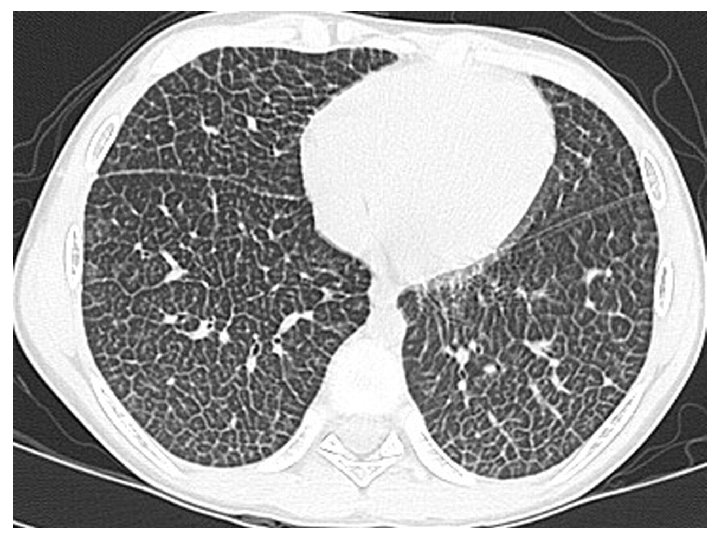

Radiographie thoracique

Just da Costa e Silva E. Pediatr Radiol 2007.